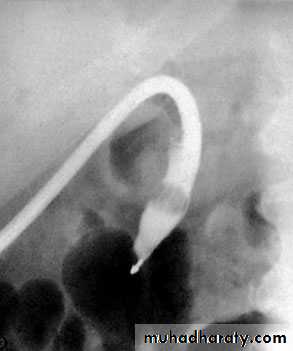

NORMAL ERCP

Endoscopic retrograde cholangiopancreatographydemonstrating stone obstructing the common bile duct (arrow